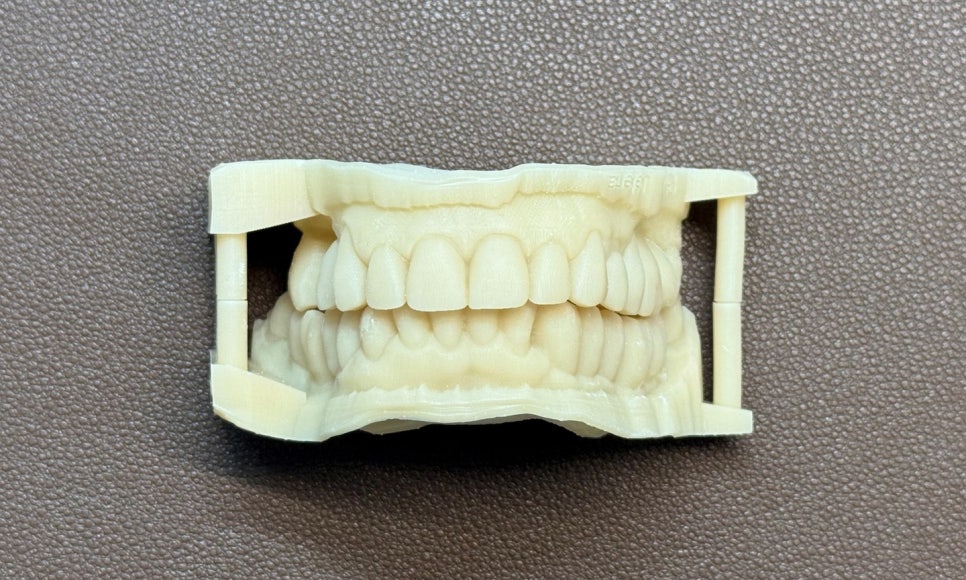

3D 프린팅 모델 - 연세정원치과

보다 정확한 상담을 위해 치료 전 3D 구강 스캔을 진행하였고, 디지털 상에서 최종 보철 형태를 왁스업 디자인한 후 3D 프린팅 모델을 제작하여 환자분과 2차 상담을 진행하였습니다. 환자분께서 1차적으로 디자인에 만족하셔서, 같은 날 기존 보철을 제거하고 동일한 디자인의 임시치아를 해드렸습니다.